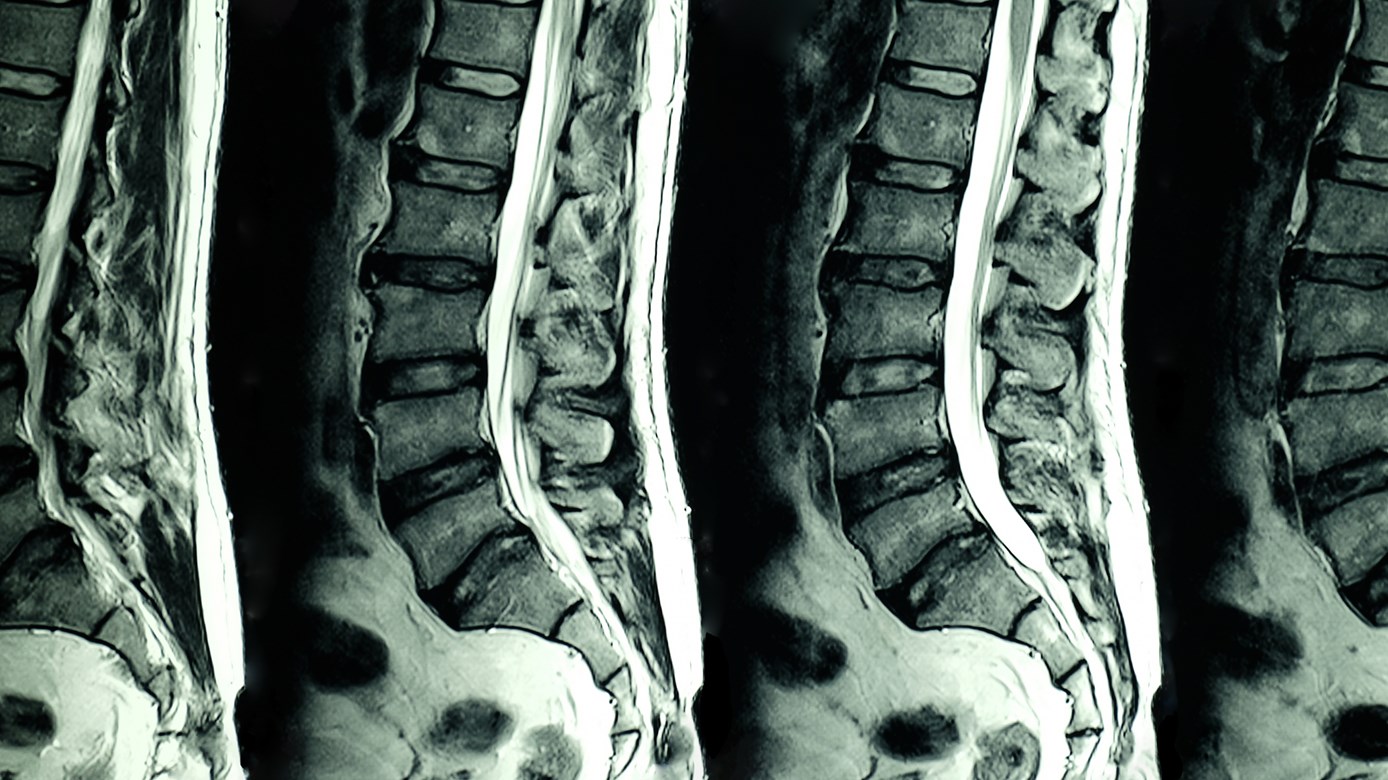

The patient has an injury to the cervical spine, lumbar spine or knee that meets the criteria outlined in the MRI Clinical Pathways.

- Lumbar Spine diagnostic imaging pathway